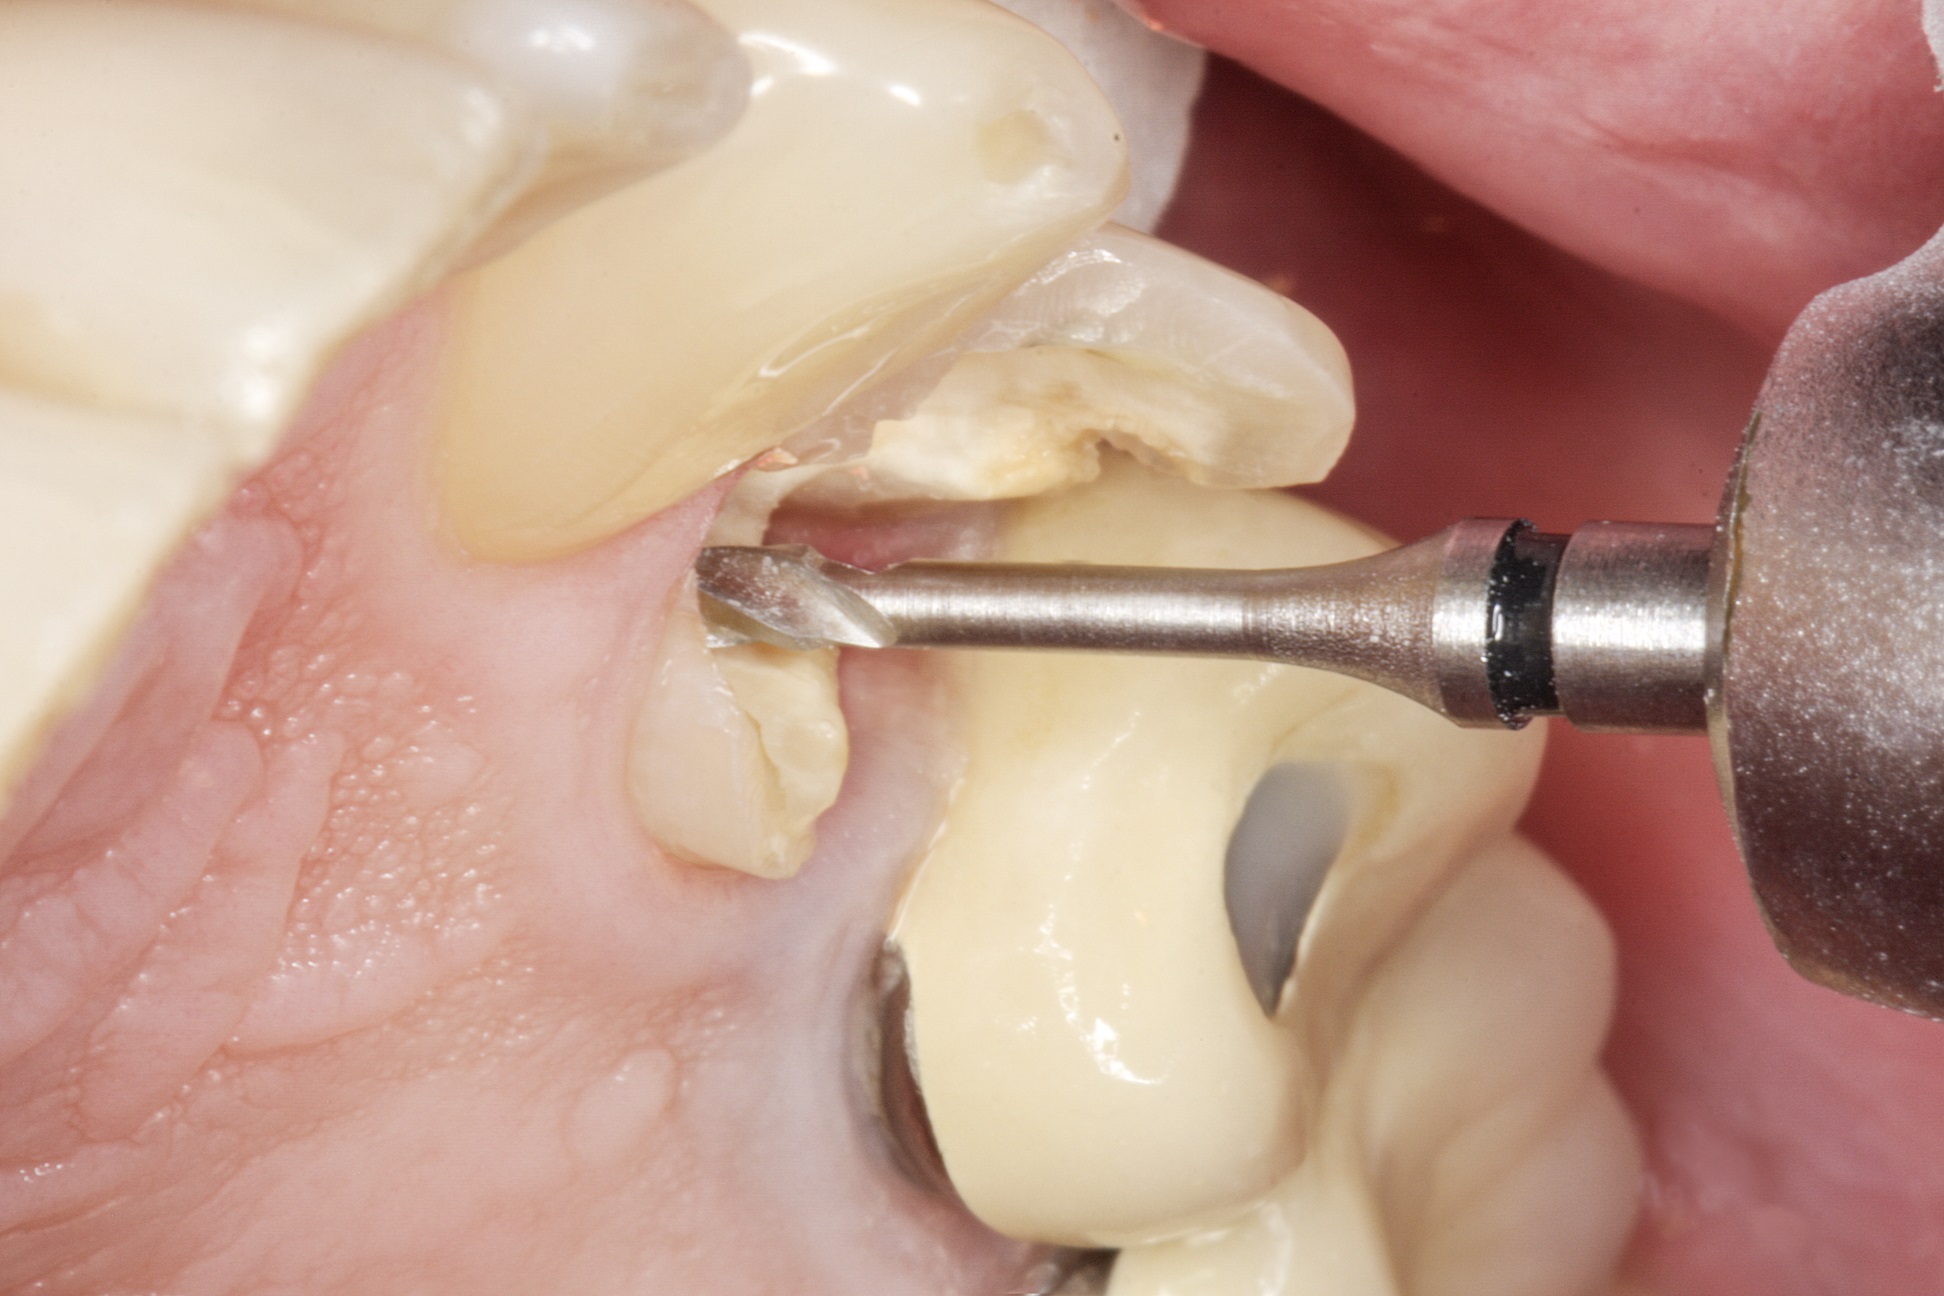

Видаляємо наявну керамічну накладку і невелику зону

каріозного ураження. Знаходимо щічний та язичний канали. За допомогою свердла

для штифтів, що є у комплекті LuxaPost, у кожному каналі створюємо ложе для

штифта глибиною 10-11 мм (рис. 2 і 3).

Фото 2. Кореневі канали після видалення матеріалу для

обтурації.

Фото 3. Робота зі свердлами LuxaPost для створення ложа для штифтів.